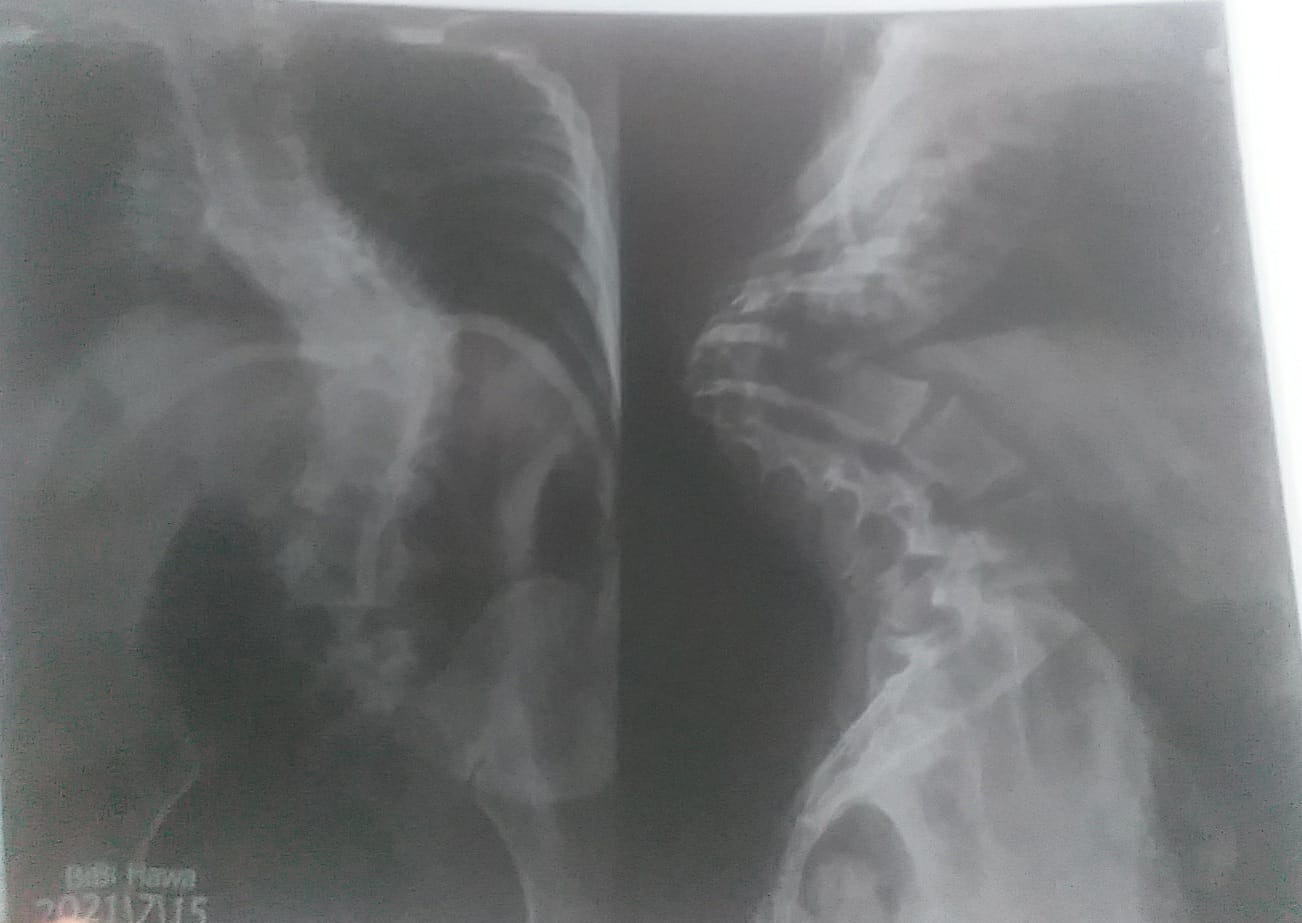

She suffers from severe scoliosis and kyphosis, a dangerous spinal deformity that places extreme pressure on her entire body.

The curvature of Hawa’s spine has reached approximately 120 degrees—a critically severe condition that compresses her chest and significantly restricts her lungs.

Doctors have clearly warned that without urgent specialized spinal surgery, Hawa faces a very high risk of spinal cord damage, permanent paralysis, and life-threatening pressure on her heart and lungs.

The only way to save her life is immediate spinal surgery with the implantation of metal rods.